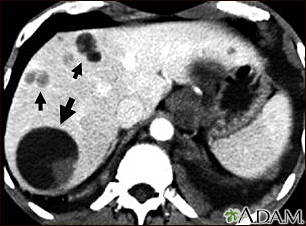

Liver echinococcus - CT scanBackLiver echinococcus - CT scanThis upper abdominal CT scan shows multiple cysts in the liver, caused by dog tapeworm (echinococcus). Note the large circular cyst (seen on the left side of the screen) and multiple smaller cysts throughout the liver. E-mail FormEmail ResultsName:Email address:Recipients Name:Recipients address:Message: